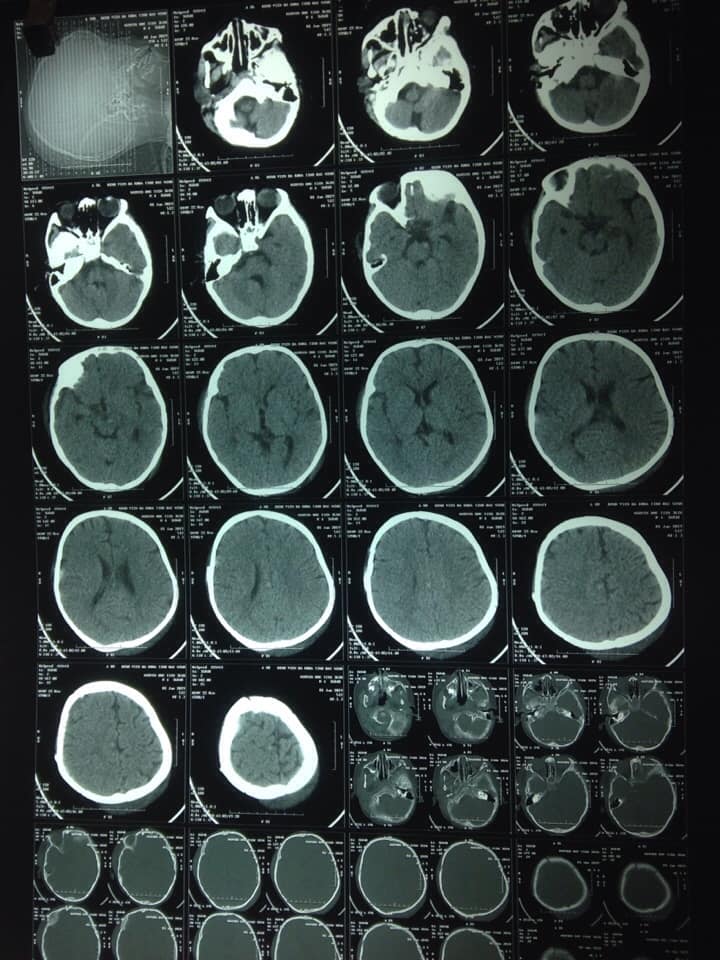

'Hình ảnh phim cắt lớp vi tính sọ sau phẫu thuật |

Ngay lập tức , các bác sĩ đã hội chẩn và mổ cấp cứu lấy khối máu tụ cho bệnh nhi. Ca mổ hoàn thành sau 2 giờ với sự cố gắng và đầy trách nhiệm của cả bác sỹ phẫu thuật và kíp gây mê. Sau phẫu thuật, bệnh nhi được hồi sức, thở máy, truyền máu, dùng thuốc, theo dõi. Đến sáng ngày 30 tháng 12 năm 2018, trẻ tỉnh, mở mắt tự nhiên, tự thở đều, đã nói được và nhận được người thân. Cả gia đình cháu cảm thấy rất hạnh phúc và những nụ cười xuất hiện làm xua tan đi nỗi lo lắng, sự mệt mỏi và cả thời tiết giá lạnh bên ngoài.